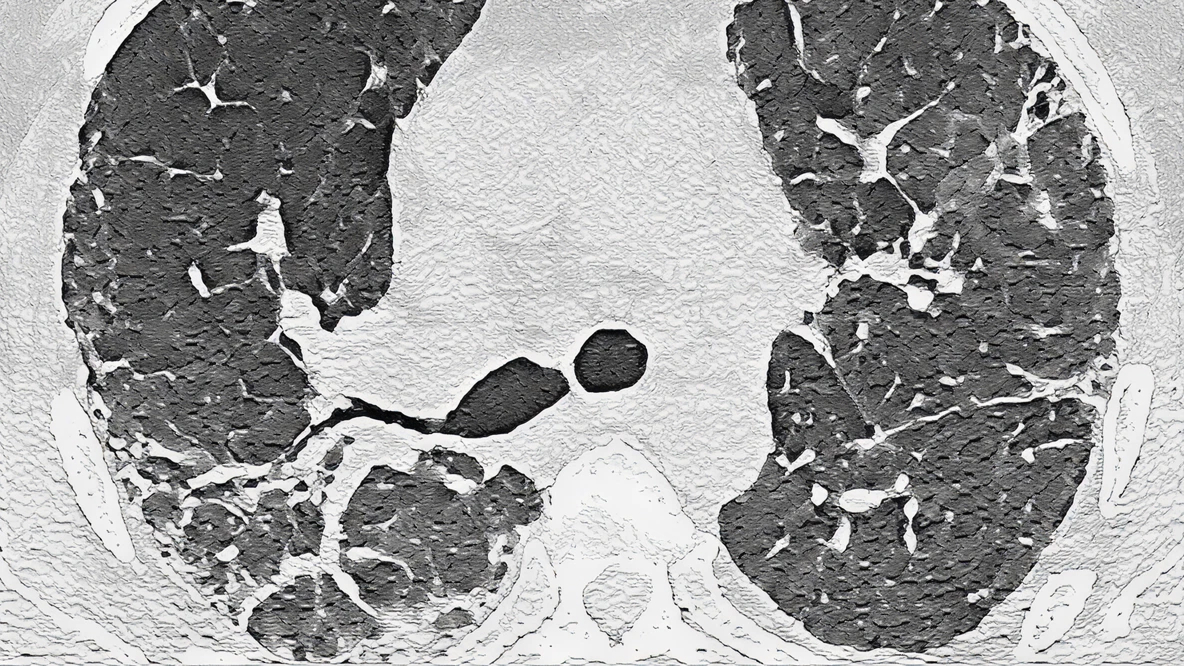

cHP

Example of cHP pattern on HRCT

Podopłucnowe pogrubienie siateczkowe, pułapki powietrzne i trakcyjne rozstrzenia oskrzeli

Znaczenie wpływu cHP na pacjentów